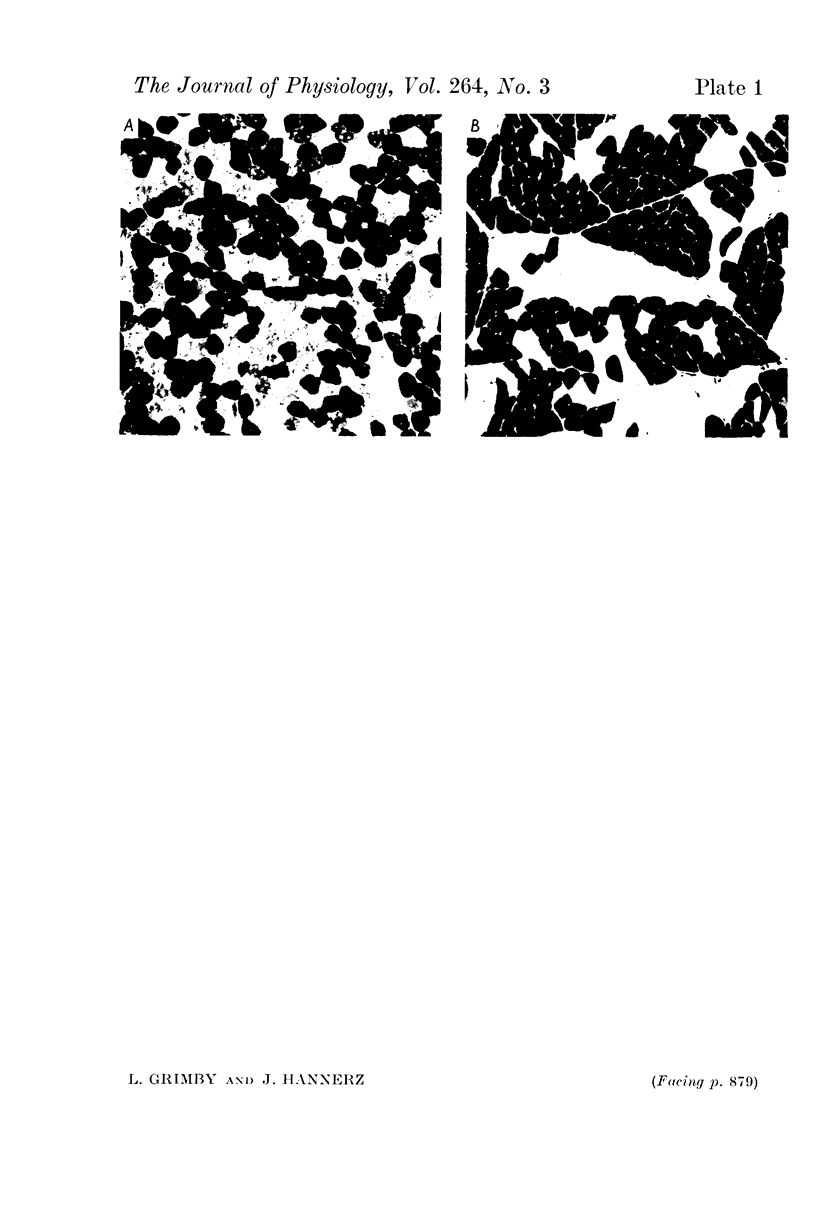

1. The discharge properties of individual motor units in different modes of voluntary contraction were studied with electromyographic techniques in the short toe extensor muscle of normal man. 2. The short toe extensor muscle consisted of type I and type II muscle fibres in about equal proportion. In some subjects there was type-grouping so that recordings with sufficient selectivity could easily be obtained. 3. Certain motor units could be driven continuously, attained regular firing intervals even at a firing rate of 10/sec, increased slowly in firing rate with increase in contraction strength, had maximum firing rate below 30/sec during sustained contraction but above 60/sec in twitch contraction. 4. Other motor units could not be dirven continuously, did not fire repeatedly at rates below 20/sec, increased rapidly in firing rate with increase in contraction strength and attained firing rates above 100/sec. 5. There were intermediate forms between continuously firing low frequency motor units and intermittently firing high frequency motor units. 6. In a prolonged contraction of constant strength only continuously firing motor units were active. 7. On rapid accelerations, however, both continuously and intermittently firing motor units were active and played about the same role. 8. This applied also to prolonged series of accelerations as in rhythmically alternating movements. 9. In twitch contractions selective activation of intermittently firing motor units occurred if the muscle was relaxed prior to the twitch and great effort was used to elicit the twitch and minimum duration of the twitch was intended. 10. It is suggested that continuously firing low frequency motor units have type I muscle fibres and intermittently firing high frequency units have type II muscle fibres and that the order of recruitment and the relative roles of the two motor unit types are adapted to the mode of contraction.

- Burke R. E., Levine D. N., Tsairis P., Zajac F. E., 3rd Physiological types and histochemical profiles in motor units of the cat gastrocnemius. J Physiol. 1973 Nov;234(3):723–748. doi: 10.1113/jphysiol.1973.sp010369. [DOI] [PMC free article] [PubMed] [Google Scholar]